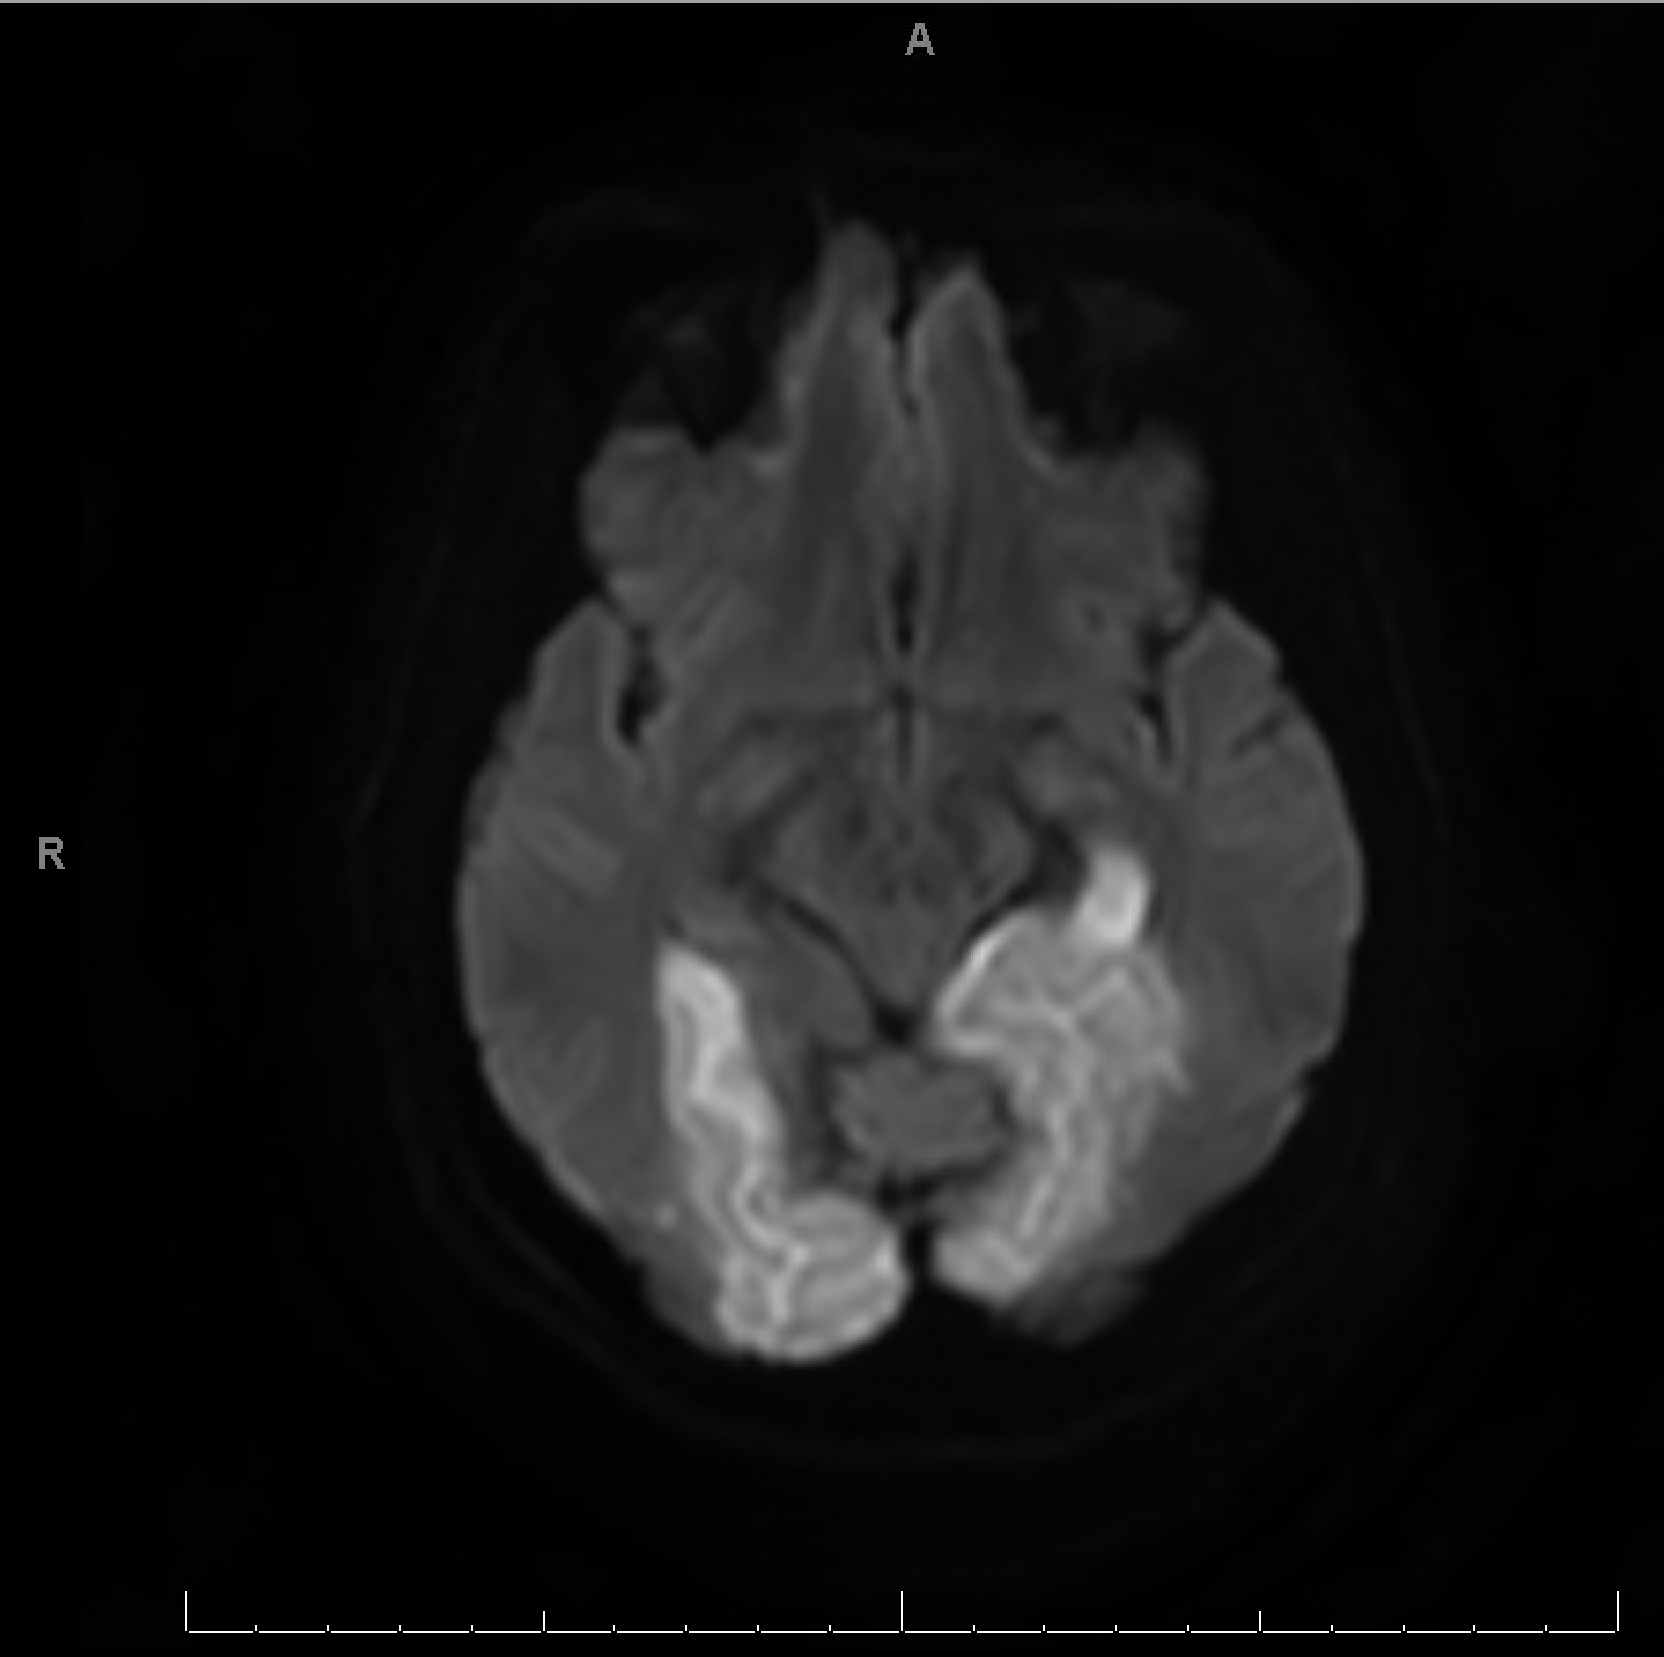

CTA revealed bilateral PCA stenosis, likely due to vasospasm. MRI brain showed bilateral occipital, left mesial temporal, and right cerebellar vasogenic edema with areas of restricted diffusion and microhemorrhages, supporting the diagnosis of PRES. Workup for infection, vasculitis, and autoimmune encephalitis was negative. Hypertensive emergency was suspected as the precipitating factor.

This case underscores the diagnostic complexity of PRES, which can mimic stroke, infection, or structural lesions. Imaging, particularly MRI, is pivotal in distinguishing PRES from infarction. The presence of seizures, encephalopathy, and visual disturbances in the setting of malignant hypertension should prompt immediate consideration of PRES, especially when imaging suggests posterior white matter involvement. This case highlights the urgency of BP control and the need for a multidisciplinary approach, including neurology, radiology, and critical care, to prevent long-term neurological sequelae.